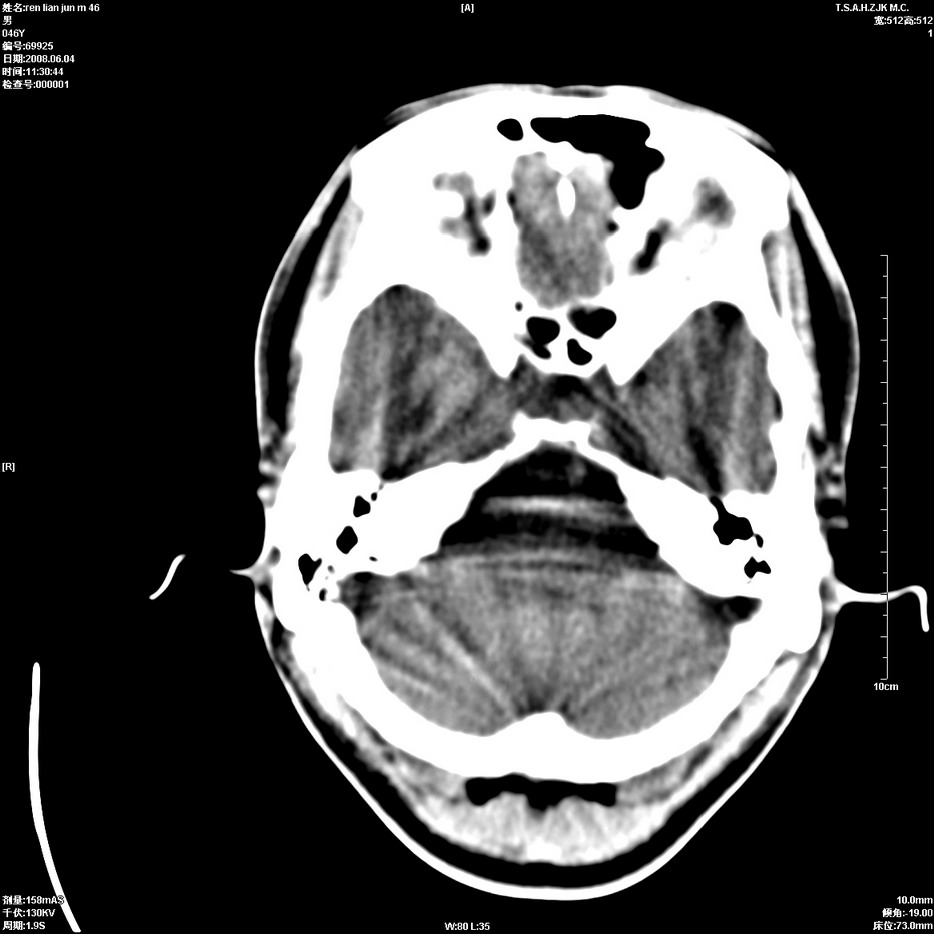

以下是引用qiu999在2008-6-5 17:14:00的发言:[br]考虑右肺中心型肺癌.颅内应做增强检查.

以下是引用形影不离在2008-6-5 19:18:00的发言:[br]右肺中心型肺癌并纵隔及左侧腋窝淋巴结转移,颅内应做增强检查。

以下是引用杀毒软件在2008-6-5 18:33:00的发言:[br]支持考虑右肺中心型肺癌,颅内病变是不是转移,不好说